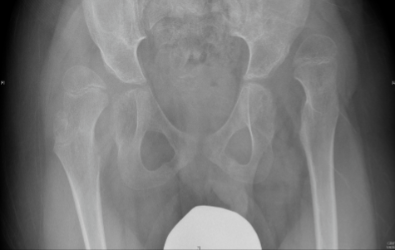

Children with cerebral palsy which are non-walkers need to be screened for hip dislocation. Hip dislocation is common in children with cerebral palsy that are restricted in wheelchairs.  Prevention of hip dislocation is important because it causes severe pain, lower limb deformities and scoliosis. In many countries universal pre-symptomatic hip screening is performed which has resulted in significant reduction in the number of hip dislocations. It is therefore recommended that regular clinical and radiological assessment is performed in children with cerebral palsy that are not able to walk.  In order to avoid hip dislocation the doctor depending on clinical and radiological assessment in each patient can recommend physiotherapy or orthotic treatment, Botox injections or surgical intervention in order to release soft tissues. However, when hip dislocation results in femoral head uncovering of more than 40%, surgical intervention is required in order to reduce the hip, usually with a femoral and/or a pelvic osteotomy.

The x-rays below are of a child with cerebral palsy (a non-walker) with bilateral hip dislocation and severe pain. The patient underwent bilateral femoral and pelvic osteotomies in order to reduce the hips.

Pre-operative